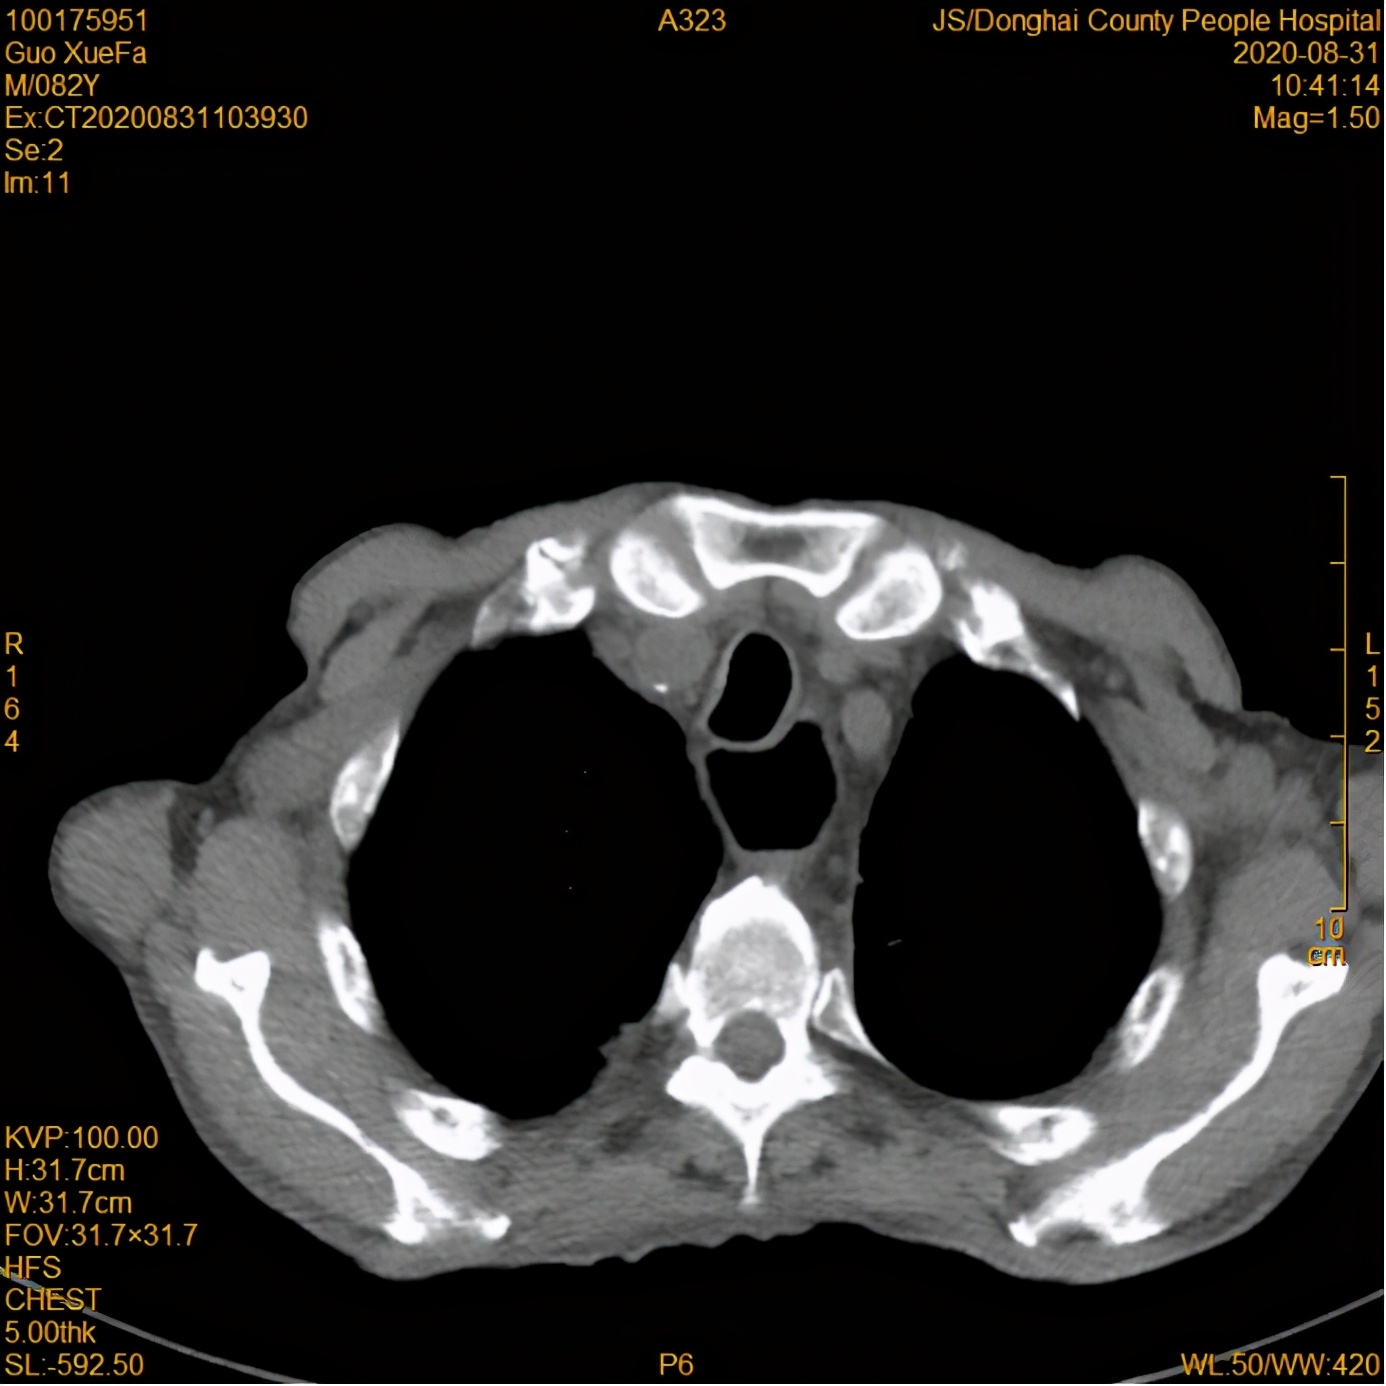

经过了6个月的放疗,复查食管钡透及胸部CT与前片对比提示食管肿瘤退缩明显,胸腔积液消失,局部肺不张亦复张。

放疗后